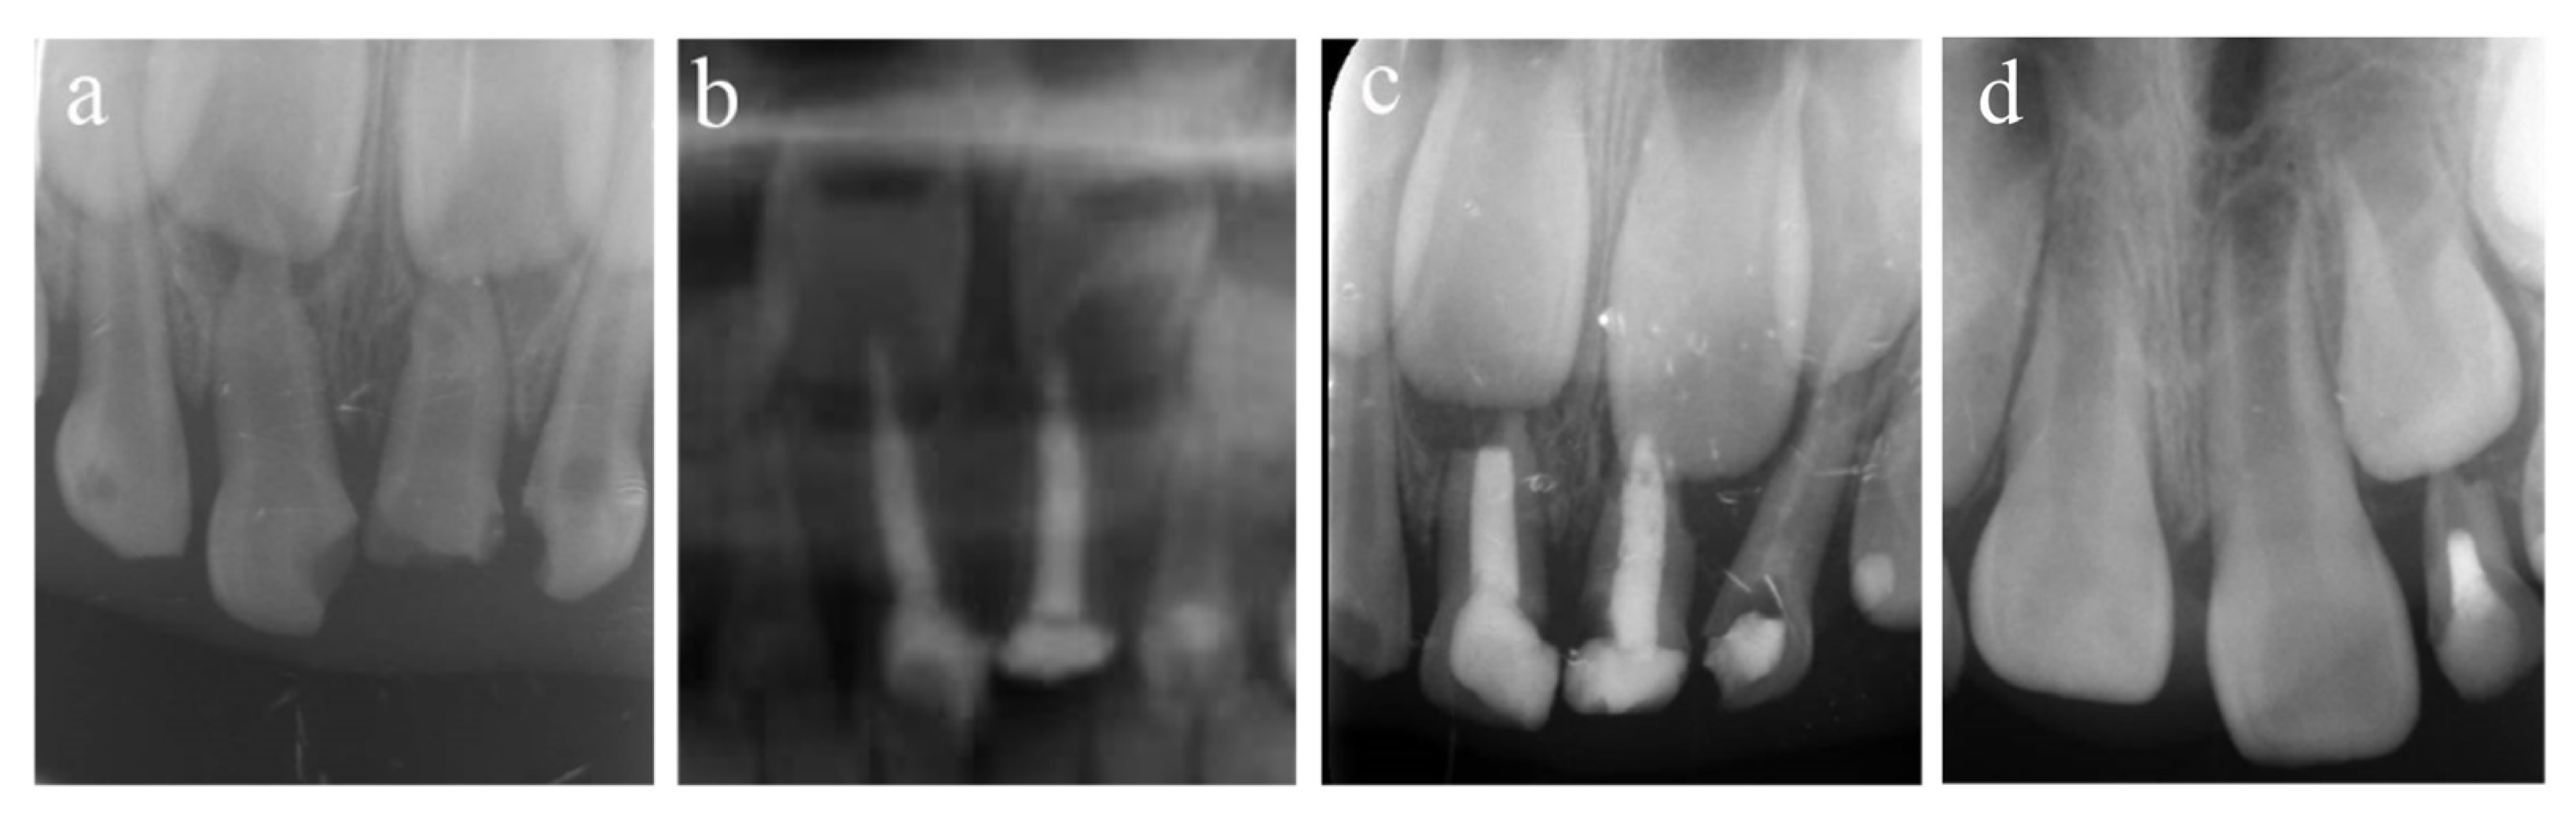

Figure 1.

#51 and #61 were treated with pulpectomies under DGA with a 51-month follow-up period (52-month-old male child). (a) The radiograph before treatment and #51 revealed periapical radiolucency. (b) One week later, the postoperative radiograph showed optimal filling in both teeth. (c) Twenty-two months after the treatment, radiography showed physiological root resorption. (d) Fifty-one months after treatment, the permanent upper incisors erupted normally. All pulpectomies succeeded.